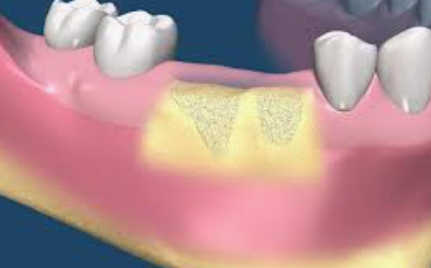

임플란트 뼈이식 혹은 골이식은 뼈 조직을 삽입 (이식)하는 수술입니다. 치과 임플란트의 맥락에서 뼈 이식은 턱뼈의 높이 또는 너비를 증가시켜 임플란트를 위한 안정적인 기반을 제공하는 것을 목표로 하는데요. 이 임플란트 뼈이식 시술은 치주질환, 발치, 외상, 노화 등으로 골소실이 있는 환자에게 필요한 경우가 많습니다.

임플란트는 턱뼈가 임플란트와 융합되는 과정인 안정성과 골유착을 위해 일정량의 뼈가 꼭 필요합니다. 뼈가 부족하면 시간이 지남에 따라 임플란트가 실패할 수 있습니다. 임플란트 뼈이식은 뼈의 양과 질을 향상시켜 임플란트의 수명을 보장함으로써 치과 임플란트 수술의 성공률을 높일 수 있기 때문에 아주 중요합니다.